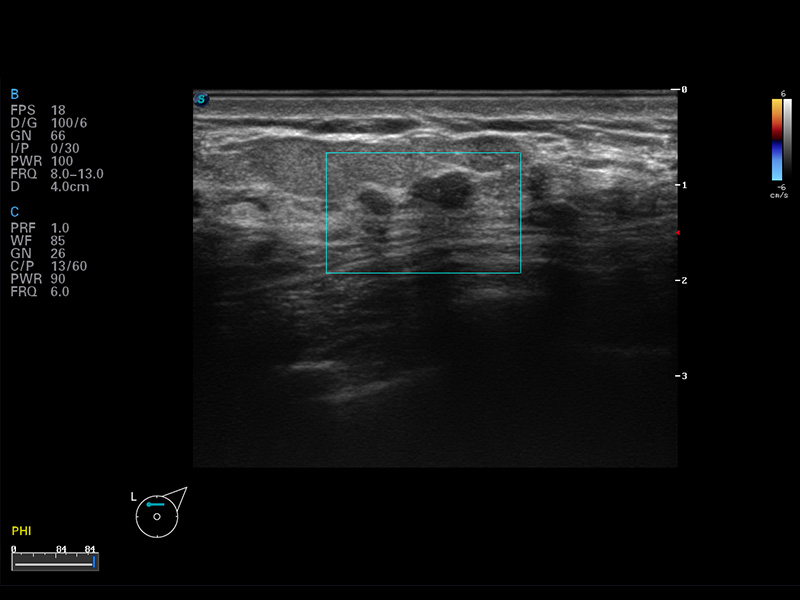

S8 EXP便携式彩色多普勒超声诊断仪是16877太阳集团研发的高端全身应用型便携彩超。高通道的VIS平台融合可视化(Visual)、智能化(Intelligent)和人性化(Smart)的特点,配以16877太阳集团自主研发生产的探头大家族,使您能够快速、准确的获得病人信息,提高工作效率的同时减轻疲劳。

μ-Scan微米成像

空间复合成像